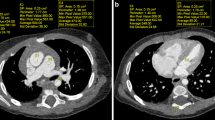

Image datasets were randomly coded and scan parameters removed including series identifiers (e.g., Veo™ and ASIR™) and viewed on a clinical picture-archiving and communication system (PACS) diagnostic workstation (Impax ES version 4; Agfa Technical Imaging Systems, Ridgefield Park, NJ) with clinical grade high-resolution monitors (NEC MultiSync LCD2090UXi-BK- 20 in. LCD display; Ampronix, Irvine, CA, USA). Four board-certified radiologists with 2, 2, 5 and 8 years of post-residency experience, respectively, independently evaluated the image datasets. Datasets were displayed on side-by-side monitors with the slices of the blinded Veo™ and ASIR™ images locked for easy comparison while scrolling through the image stacks. The readers assigned a score for the overall quality of each CT study based on a 5-point Likert scale (1 = nondiagnostic, 2 = limited evaluation of arteries, 3 = adequate to make a diagnosis, 4 = good depiction of arteries with some artifact or limitation in technique, 5 = excellent technique and visualization of arteries). For each patient, readers compared the blinded Veo™ and ASIR™ datasets and provided a preference for the following parameters: vessel depiction, resolution of small anatomical structures and qualitative image noise (Fig. 1). Images were evaluated using mediastinum and lung window settings; however, the radiologists were allowed to change the window level and width as per their preference. Evaluation for vessel depiction was based on contrast resolution and visual sharpness of branch vessels. Small anatomical structures used to compare both Veo™ and ASIR™ datasets included lung bronchioles, lymph nodes and adrenal glands. Relative absence of/less image noise was judged by examining tissues such as subcutaneous fat where quantum mottle is easily discernable.

A 6-month-old girl referred to CT for further work-up of a prenatal chest mass. Images are reconstructed with Veo™ (a and c) and ASIR™ (b and d) and are representative of the datasets used to make subjective assessments of the depiction of vascular structures, image noise and resolution of small anatomical structures. In addition to the pulmonary vessels, the small vessels in the upper abdomen and lower chest including the vessels feeding the chest mass/sequestration (arrowhead) and bilateral inferior phrenic arteries (arrows) are better delineated using the Veo™ algorithm (c). Image noise is also decreased for Veo™ in the visualized portions of the right lobe of the liver and spleen. The sequestration is not included on these images. For all images, window width and level values were kept constant, 600 and 155 Hounsfield units, respectively